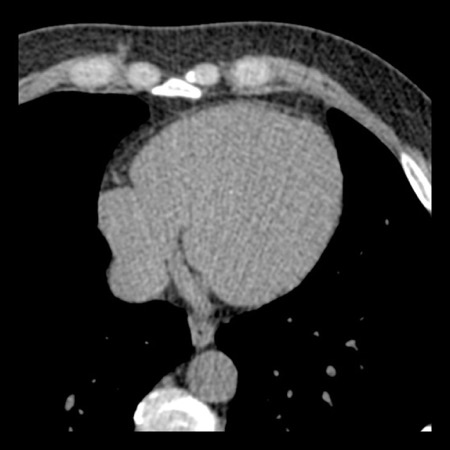

case 4 – CAD-RADS 3/P1/I+ thrombus left ventricle

First, scroll through the CTA images.

How would you describe the findings on the coronary CTA?

The findings are:

- Moderate (50-69%)

stenosis in the proximal LAD caused by a non-calcified plaque. - Variant of

sinoatrial (SA) nodal artery. The artery usually arises from the RCA as a second

branch after the conus artery, however in this case it arises from the LCX,

courses behind the aorta, anastomosing with the right atrium and with a small

branch supplies the SA-node of the heart. - Thrombus in the

apex of the left ventricle. - CTP was performed

in this patient. CTP showed a perfusion defect at stress imaging in the

territory of the LAD (I+), at rest no perfusion defect was visible.

This patient classifies as CAD-RADS 3/P1/I+, which means

this patient requires further investigation.